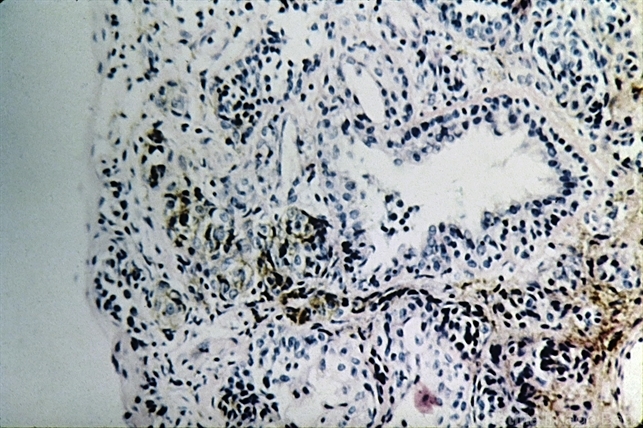

- nevus, conjunctiva, epithelial, cyst

- Nevus of the conjunctiva. Clusters of benign nevus cells surround an epithelial inclusion cyst.